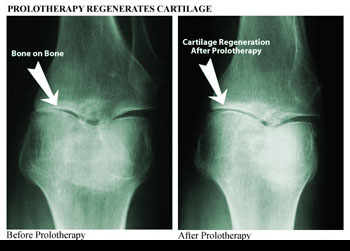

Used with permission

from Ross A Hauser, MD,

www.caringmedical.com

range of motion returns, and cartilage degeneration slows

down.

Used

with permission from Ross A Hauser, MD,

www.caringmedical.com.